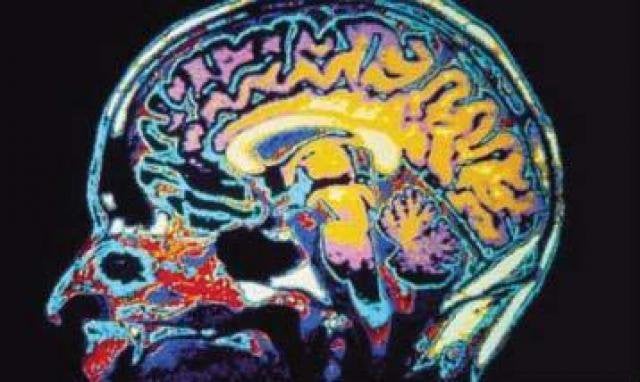

brain injury in florida

Lasting Effects of a Brain Injury

The most severe traumatic brain injuries can result in long-term cognitive, behavioral and physical disabilities. More than 5 million Americans […]